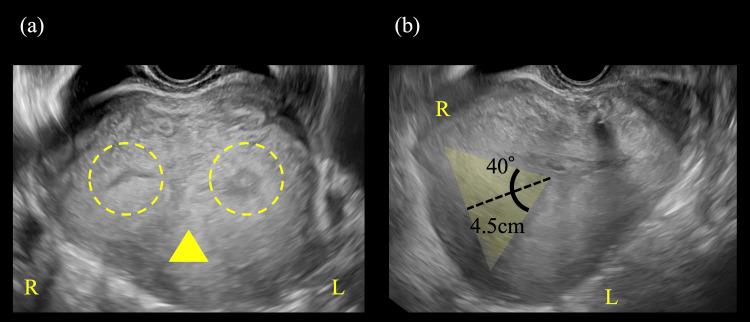

Placental attachment spanning from the anterior to the posterior uterine wall, resulting in the formation of two uterine cavities, presents a diagnostic challenge in obstetrics. Differential diagnoses include placental abruption, multiple gestations, placental variations, and uterine anomalies. Accurate prenatal identification is often difficult, especially when anomalies are not detected during early pregnancy. We report a rare case of a 27-year-old primigravid Japanese woman with a placenta spanning from the anterior to the posterior uterine wall, creating two cavities. At 35 weeks of gestation, ultrasound suggested an unusual placental position, with fetal parts located in separate cavities. At 37 weeks and three days, a cesarean section was performed for breech presentation. Intraoperatively, a partial uterine septum was palpated postplacental removal, with a planar fundus and no retroplacental hematoma. Postoperative ultrasound confirmed the diagnosis of a partial septate uterus. Although septate uterus is the most common uterine anomaly, it often remains undiagnosed in women without infertility. This case highlights the importance of considering uterine anomalies when placental morphology is atypical, especially in the absence of a prior diagnosis, as early recognition is crucial for appropriate perinatal management.

胎盘附着横跨子宫前壁至后壁,导致形成两个子宫腔,这在产科诊断中是一项挑战。鉴别诊断包括胎盘早剥、多胎妊娠、胎盘变异和子宫畸形。准确的产前诊断往往很困难,尤其是在孕早期未检测到异常时。我们报告了一例罕见病例,一名27岁的初产妇日本女性,其胎盘横跨子宫前壁至后壁,形成两个腔隙。妊娠35周时,超声提示胎盘位置异常,胎儿部分位于不同腔隙。妊娠37周零三天时,因臀位行剖宫产术。术中,胎盘取出后可触及部分子宫纵隔,子宫底部平坦,无胎盘后血肿。术后超声确诊为部分纵隔子宫。虽然纵隔子宫是最常见的子宫畸形,但在无不孕的女性中往往未被诊断。该病例强调了在胎盘形态不典型时,尤其是在未事先诊断的情况下,考虑子宫畸形的重要性,因为早期识别对于适当的围产期管理至关重要。